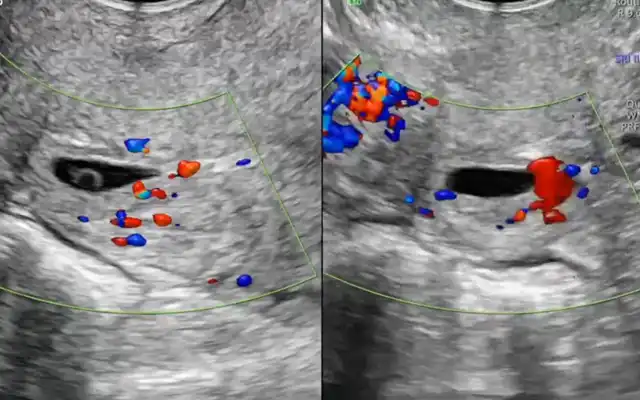

Intra Uterine Adhesions (IUA) are strings of fibrous tissue connecting opposite walls of the uterine cavity. IUA are found after control hysteroscopy in 31,3% after myomectomy, 6,7% after septectomy and 3,6% after polypectomy (4) There is a conundrum in denominations Asherman’s syndrome (Joseph Asherman 1889 – 1968) (5). He does refer first to a complete occlusion and stenosis of the cervical os, with as consequence amenorrhea but with atrophic endometrium in the cavity whilst the second syndrome is IUA characterized by painful, reduced menses and secondary infertility. Both syndromes are described after trauma in the uterine cavity under influence of pregnancy hormones. In both syndromes there is a dysfunctional endometrium more pronounced in the first syndrome (Mark Hans Emmanuel, personal communication 2021) The time to

Fig 1: The classical image of Intra Uterine adhesions (synechiae) at hysterosalpingography